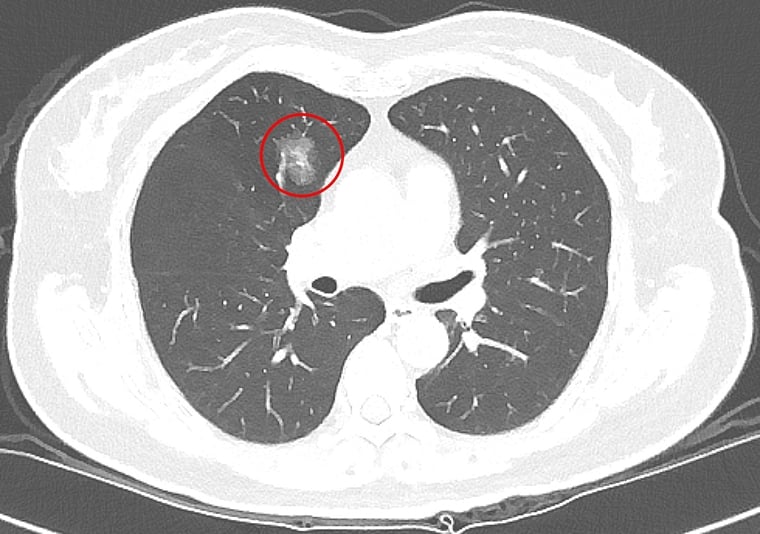

【NOW健康 楊芷晴/新北報導】隨著低劑量電腦斷層(LDCT)篩檢日益普及,越來越多民眾在健康檢查或就醫過程中發現肺部小結節,也讓「到底要不要立刻開刀」成為門診中常見疑問。台北慈濟醫院胸腔內科吳智偉醫師針對院內LDCT共6997名篩檢個案進行回溯性分析,結果發現手術切除的病灶中,有約2/3被證實是惡性腫瘤,另外1/3為良性腫瘤,由此可知小型肺部結節在影像判讀與切片診斷上極具挑戰,研究成果於今年1月獲國際期刊《International Journal of Medical Sciences》刊登。

肺癌發生率已居全國第一,影響因子包括抽菸、肺癌家族史及空氣污染等,但吳智偉醫師指出,臨床上超過一半肺癌患者其實不抽菸,因此即使沒有抽菸習慣,也不能完全輕忽風險。近年政府積極推動低劑量電腦斷層篩檢,提升肺癌早期發現及治療的機會,針對肺部小結節,臨床上雖會依據大小、影像型態、生長狀況以及病人的臨床背景進行綜合判斷,但部分良性病灶在影像上與早期肺癌相似,有些早期惡性病灶則生長緩慢、不易立即判別。

有鑑於篩檢發現的小型肺結節在診斷與後續處置上仍有不少挑戰,吳智偉醫師回溯分析台北慈濟醫院2013年至2018年間共6997名LDCT篩檢者資料,並追蹤至2023年,探討篩檢發現之肺腫瘤的生長模式、病理診斷、診斷時程及電腦斷層導引切片的準確性。研究結果顯示,接受手術或切片的腫瘤中,約有2/3為惡性腫瘤,並以肺腺癌最為常見;而其餘1/3的良性病理發現則是以纖維化和炭粒沉積最常見。

吳智偉醫師說明,纖維化通常是肺部過去曾受感染或發炎後留下的疤痕,炭粒沉積則是空氣中的污染微粒被吸入肺部後堆積形成的結節。這兩類良性病灶之所以難以分辨,在於影像上與早期肺癌相似,因此即使經過多重評估,目前的醫學仍難以僅憑影像,準確區分良性或惡性。此外,約有13%的良性腫瘤,在追蹤的過程中以新發生的病灶(de novo)的形式被發現,讓影像的初期判斷更加艱難。

以許女士為例,沒有抽菸習慣,也沒有肺癌家族史,卻在64歲健康檢查時,從低劑量電腦斷層(LDCT)檢查中發現1.2公分的肺部結節,之後持續在胸腔內科門診追蹤。7年後,許女士71歲時,結節增大至1.4公分,因為擔憂,她與醫師討論後轉至胸腔外科手術,病理結果確診為第一期肺腺癌。由於屬早期肺癌,術後不需化療,追蹤至今恢復良好,無併發症。對此,吳智偉醫師說明,許多肺部結節通常需要追蹤很長的時間,才會有些微變化(1年約長大0.1cm),臨床上會根據變化的型態進一步評斷處置方式。

極早期的結節因為太小,無法經由穿刺切片確認屬性。吳智偉醫師提醒,發現肺結節不必過度恐慌,也不代表一定要立刻動刀,目前國內外的共識是以大小0.8公分作為最基礎的判斷準則,在困難判讀的情況下,建議須定期追蹤。若在追蹤期間出現變大或影像特徵改變,建議與醫師討論或進一步評估手術時機,通常會有機會在零期或第一期及早治療。